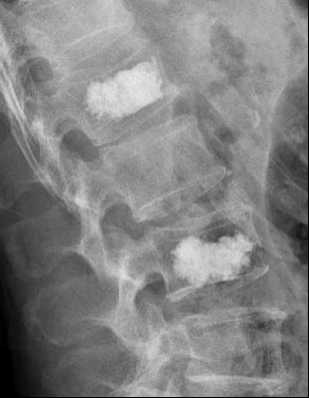

图 3术后拍片

8月7日,患者孙某某,男,76岁,因腰1、腰3椎体压缩性骨折来我院住院治疗。病人在翻身、坐起和躺下时出现明显疼痛,严重影响生活和正常的康复治疗。病人年龄大,身体条件差,左上肢僵硬处在胸前位不能俯卧,但老年人疼痛症状又非常明显,与其家属交流后决定行侧卧位椎体成形术(PVP)。手术于8月8日顺利完成。术后第2天,病人即可下地行走。

经皮穿刺椎体成形术,属于微创手术,是通过向病变椎体内注入骨水泥(聚丙烯酸甲酯)达到强化椎体的技术。在患者背部做一约3mm的切口,在X线监护下经皮肤穿刺导管进入椎体,将骨水泥注入椎体内稳定骨折椎体,防止进一步塌陷,明显缓解疼痛。